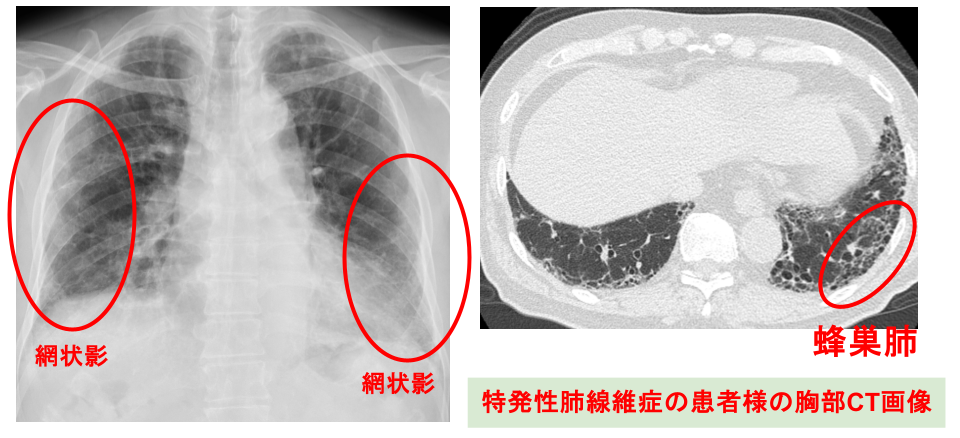

②画像検査

胸部レントゲンや胸部CT検査を行います。レントゲンやCTでは、網状影(もうじょうえい)やすりガラス影などのほかに、進行すると蜂巣肺(ほうそうはい)と呼ばれる蜂の巣に似た所見がみられることがあります。